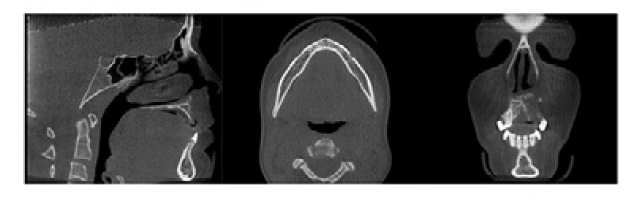

A

Sagittal, axial, coronal